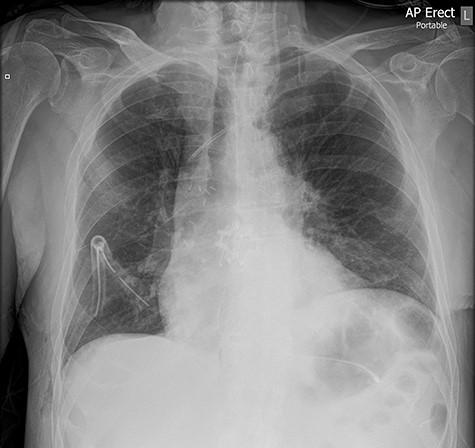

The left basal chest drain was removed without incident on Day 5. However, the nurse encountered resistance during attempted removal of the right basal chest drain. The intern was subsequently notified. Resistance was also encountered by the intern during a further attempt to remove the chest drain. A chest X-ray performed earlier in the day was reviewed (Fig. 2). It demonstrated kinking of the drain around a rib. The intern altered the direction of traction in order to account for the kinking but, during gentle traction, the chest drain fractured at the 14-cm mark (Fig. 3) and became retained within the right hemithorax (Fig. 4). The thoracostomy wound was closed and senior help was immediately sought.

Chest X-ray demonstrating the retained chest tube segment on the right side.